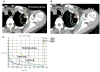

Materials and methods: We delivered SBRT to 27 patients, 13 with Stage I and 14 with isolated recurrent NSCLC. A central/superior location was defined as being within 2 cm of the bronchial tree, major vessels, esophagus, heart, trachea, pericardium, brachial plexus, or vertebral body, but 1 cm away from the spinal canal. All patients underwent four-dimensional computed tomography-based planning, and daily computed tomography-on-rail guided SBRT. The prescribed dose of 40 Gy (n = 7) to the planning target volume was escalated to 50 Gy (n = 20) in 4 consecutive days.